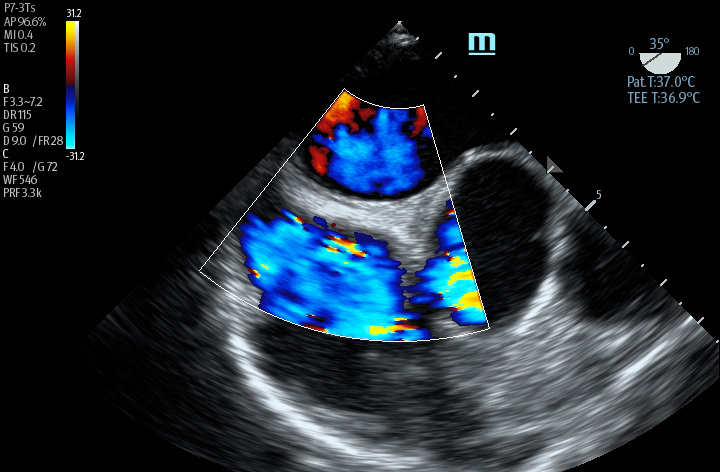

The TE7 Ultrasound System Crystal Series 2.0 is the system of choice from routine point-of-care exams to extreme situations when every second counts. With best-in-class image quality, a sleek form factor, and breakthrough needle visualization advancements, the TE7 System is designed to provide superior performance for rapid, confident exams and procedures in the fast paced, point of care environment.

Smart VTI

Automated measurement of the Velocity Time Integral (VTI) and Cardiac Output (CO), enables rapid assessment of cardiac function. This software automatically locates color box and Pulse Wave Doppler (PW) sample line in real time. A graph of parameter trends for CO, Stroke Volume (SV) and VTI is produced to guide decision-making.